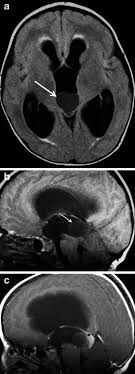

A Showing The Pineal Gland Cyst And Its Relationship To The Download Scientific Diagram

Brain Magnetic Resonance Imaging Mri Of A 40 Year Old Patient Showing Download Scientific Diagram

Pineal Cyst In A 6 Year Old Girl Causing Diplopia Headache And Download Scientific Diagram